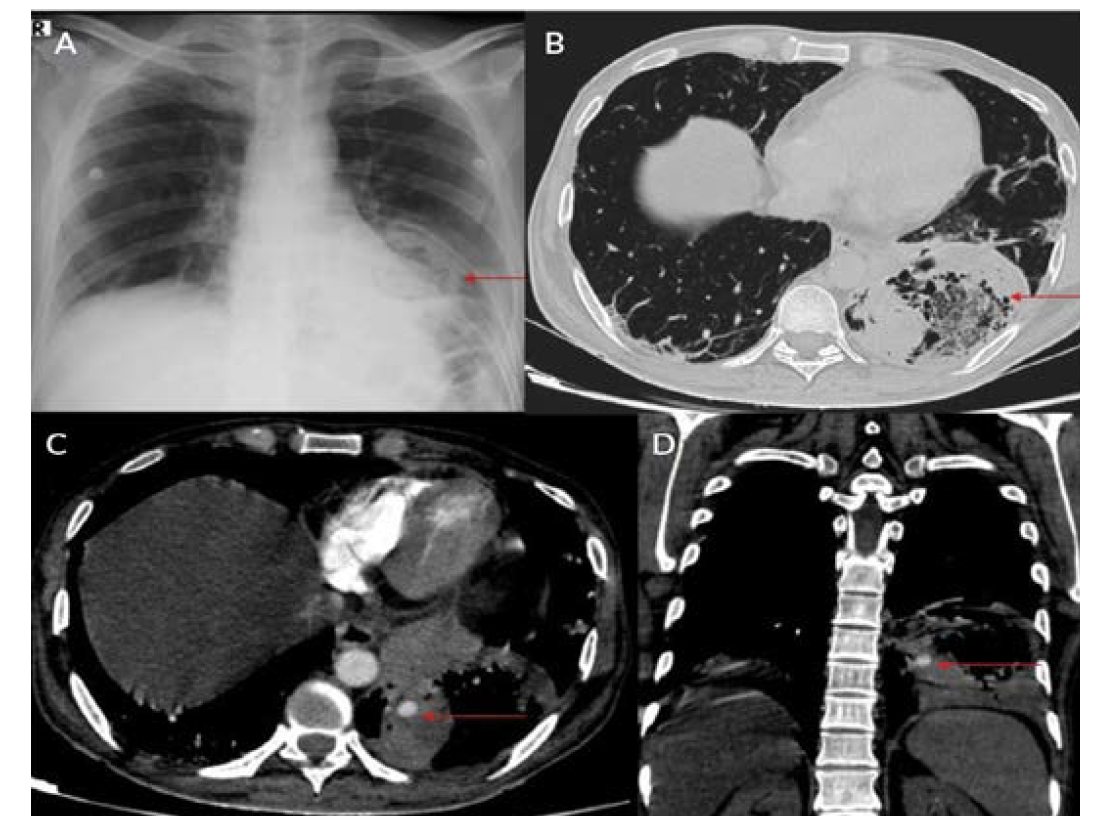

Eight patients were included during this study period; all were men between ages 34 and 61 (Table 1). Positivity to COVID-19 RTPCR test was detected over a period of 2 to 6 months prior to the acute hemorrhage. Six patients presented with massive hemoptysis; 2 presented with severe epistaxis. A contrast-enhanced computed tomography angiography was done in all patients. All 6 patients who presented with massive hemoptysis were detected to have pulmonary arterial pseudoaneurysms with associated cavitary lesions in the lungs (Figure 2). Among the 2 patients who presented with nasal bleed, 1 had a biopsy and culture-proven invasive fungal sinusitis with an internal maxillary artery pseudoaneurysm, probably of mycotic etiology. The second patient also diagnosed with invasive fungal sinusitis had multiple sinonasal debridements outside before presenting with massive epistaxis wherein a diagnosis of internal carotid artery pseudoaneurysm was made, probably secondary to iatrogenic or mycotic etiology. The presence of concomitant COVID-19 infection in these patients predisposed them to impairment of cell-mediated immunity, immune dysregulation, and a decrease in CD4 and CD8 counts, increasing their vulnerability to fungal infections. In 6 patients it was possible to obtain samples for fungal elements through biopsy. Endovascular embolization was performed under local anesthesia in 7 patients, and under general anesthesia in 1 patient. Different embolic agents were used: coils (Figures 3A and 3B), Amplatzer vascular plug (Abbott) (Figures 4A and 4B, Figures 5A and 5B), and glue (Figures 6A and 6B). However, 2 patients underwent lobectomy for extensive parenchymal disease apart from pseudoaneurysm. One patient with pulmonary artery pseudoaneurysm had contrast extravasation into the cavity during the procedure. All patients had cessation of hemorrhage. However, 2 patients required pulmonary lobectomy because of extensive parenchymal disease after embolization for the pseudoaneurysm.

COVID-19 infection has affected people worldwide since 2020 after its initial outbreak in Wuhan, China. It has caused significant mortality and morbidity, causing millions of deaths to date. COVID-19 infection is known to affect multiple organs such as the lungs, heart, brain, and skin, with the lung being most common.1 Patients with COVID-19 usually present with complaints of fever, cough, malaise, and difficulty breathing.1 Diabetes mellitus is an independent risk factor for COVID-19 infection.1 Fungal infection was a known complication following COVID-19 infection, especially in those with poorly controlled blood sugar and who have been treated with immunosuppressive agents such as steroids.2,3 Pulmonary complications following COVID-19 infection were mainly related to fibro-cavitary changes.3-5 Hemorrhage following fungal infection was mainly due to vascular involvement and formation of pseudoaneurysm.6 Patients with severe COVID-19 infection may have endothelial inflammation and secondary fungal infection, leading to pseudoaneurysm formation with a risk of increased bleeding.5,6 Fungal sinusitis following COVID-19 infection is a well-known entity that can cause bleeding due to the involvement of the internal and external carotid vessels.2,3,5 Extracranial carotid artery aneurysms are found most frequently in the common carotid artery at or near the bifurcation, less frequently in the internal carotid artery (Figures 7A and 7B), and least often in the external carotid artery.7,8 Ongoing studies of the precise molecular underpinnings of mycotic pseudoaneurysms suggest that arterial wall breakdown is likely caused by matrix-degrading enzymes produced by either seeded bacteria or inflammatory cells of the host response.6 Diabetes and fungal infections are more frequently documented, which could result in mycotic aneurysm, spontaneous rupture, and massive hemorrhage.2,3,5

Pulmonary artery pseudoaneurysm is a rare but important entity because of its high risk of life-threatening hemorrhage.2,5,9,10 Peripheral branches of the lower lobe pulmonary artery are most commonly affected.2,5,10 A pseudoaneurysm is different from a true aneurysm because there is no wall except for the hematoma that is surrounding and containing it.6,9,11,12 The etiology of a pulmonary artery pseudoaneurysm is inflammatory erosion secondary to tuberculosis (Rasmussen aneurysm), necrotizing pneumonia, bacterial endocarditis, mucormycosis, or vasculitides (Marfan syndrome, Behçet’s disease, etc.). Other causes include necrotic cavitary lung carcinoma, congenital heart disease, and traumatic injury. Iatrogenic pseudoaneurysm secondary to pulmonary artery catheter placement has also been reported.4-6,9-11 Internal maxillary artery pseudoaneurysm is rare and is more commonly encountered following trauma and iatrogenic injury (Figures 8A and 8B).7,8,13 These patients present with massive or moderate bleeds, which can lead to death in about 50% of cases if left untreated.2,4 The most common artery leading to hemoptysis is the bronchial artery, which constitutes around 80% to 90%.4,5,13 Hemoptysis related to the pulmonary artery constitutes around 10%.10,14 Multidetector computed tomography (MDCT) pulmonary angiography is the modality of choice to diagnose pulmonary artery aneurysms.2,9,10,12 It provides detailed information about the presence, number, size, shape, and origin of pulmonary artery aneurysms.2,9,10 MDCT also allows detailed assessment of the orientation and size of the aneurysmal sac and size of the neck on multiplanar reconstruction.2,10 It also gives an overall idea about the pathology, and the involved lung segment eventually helps in planning the treatment accordingly.4,10,12,14 Digital subtraction angiography has the advantage of allowing endovascular intervention at the time of diagnosis.4,12,14 Ultrasound and magnetic resonance imaging are also used in cases of aneurysms involving neck vasculature.2,14,12